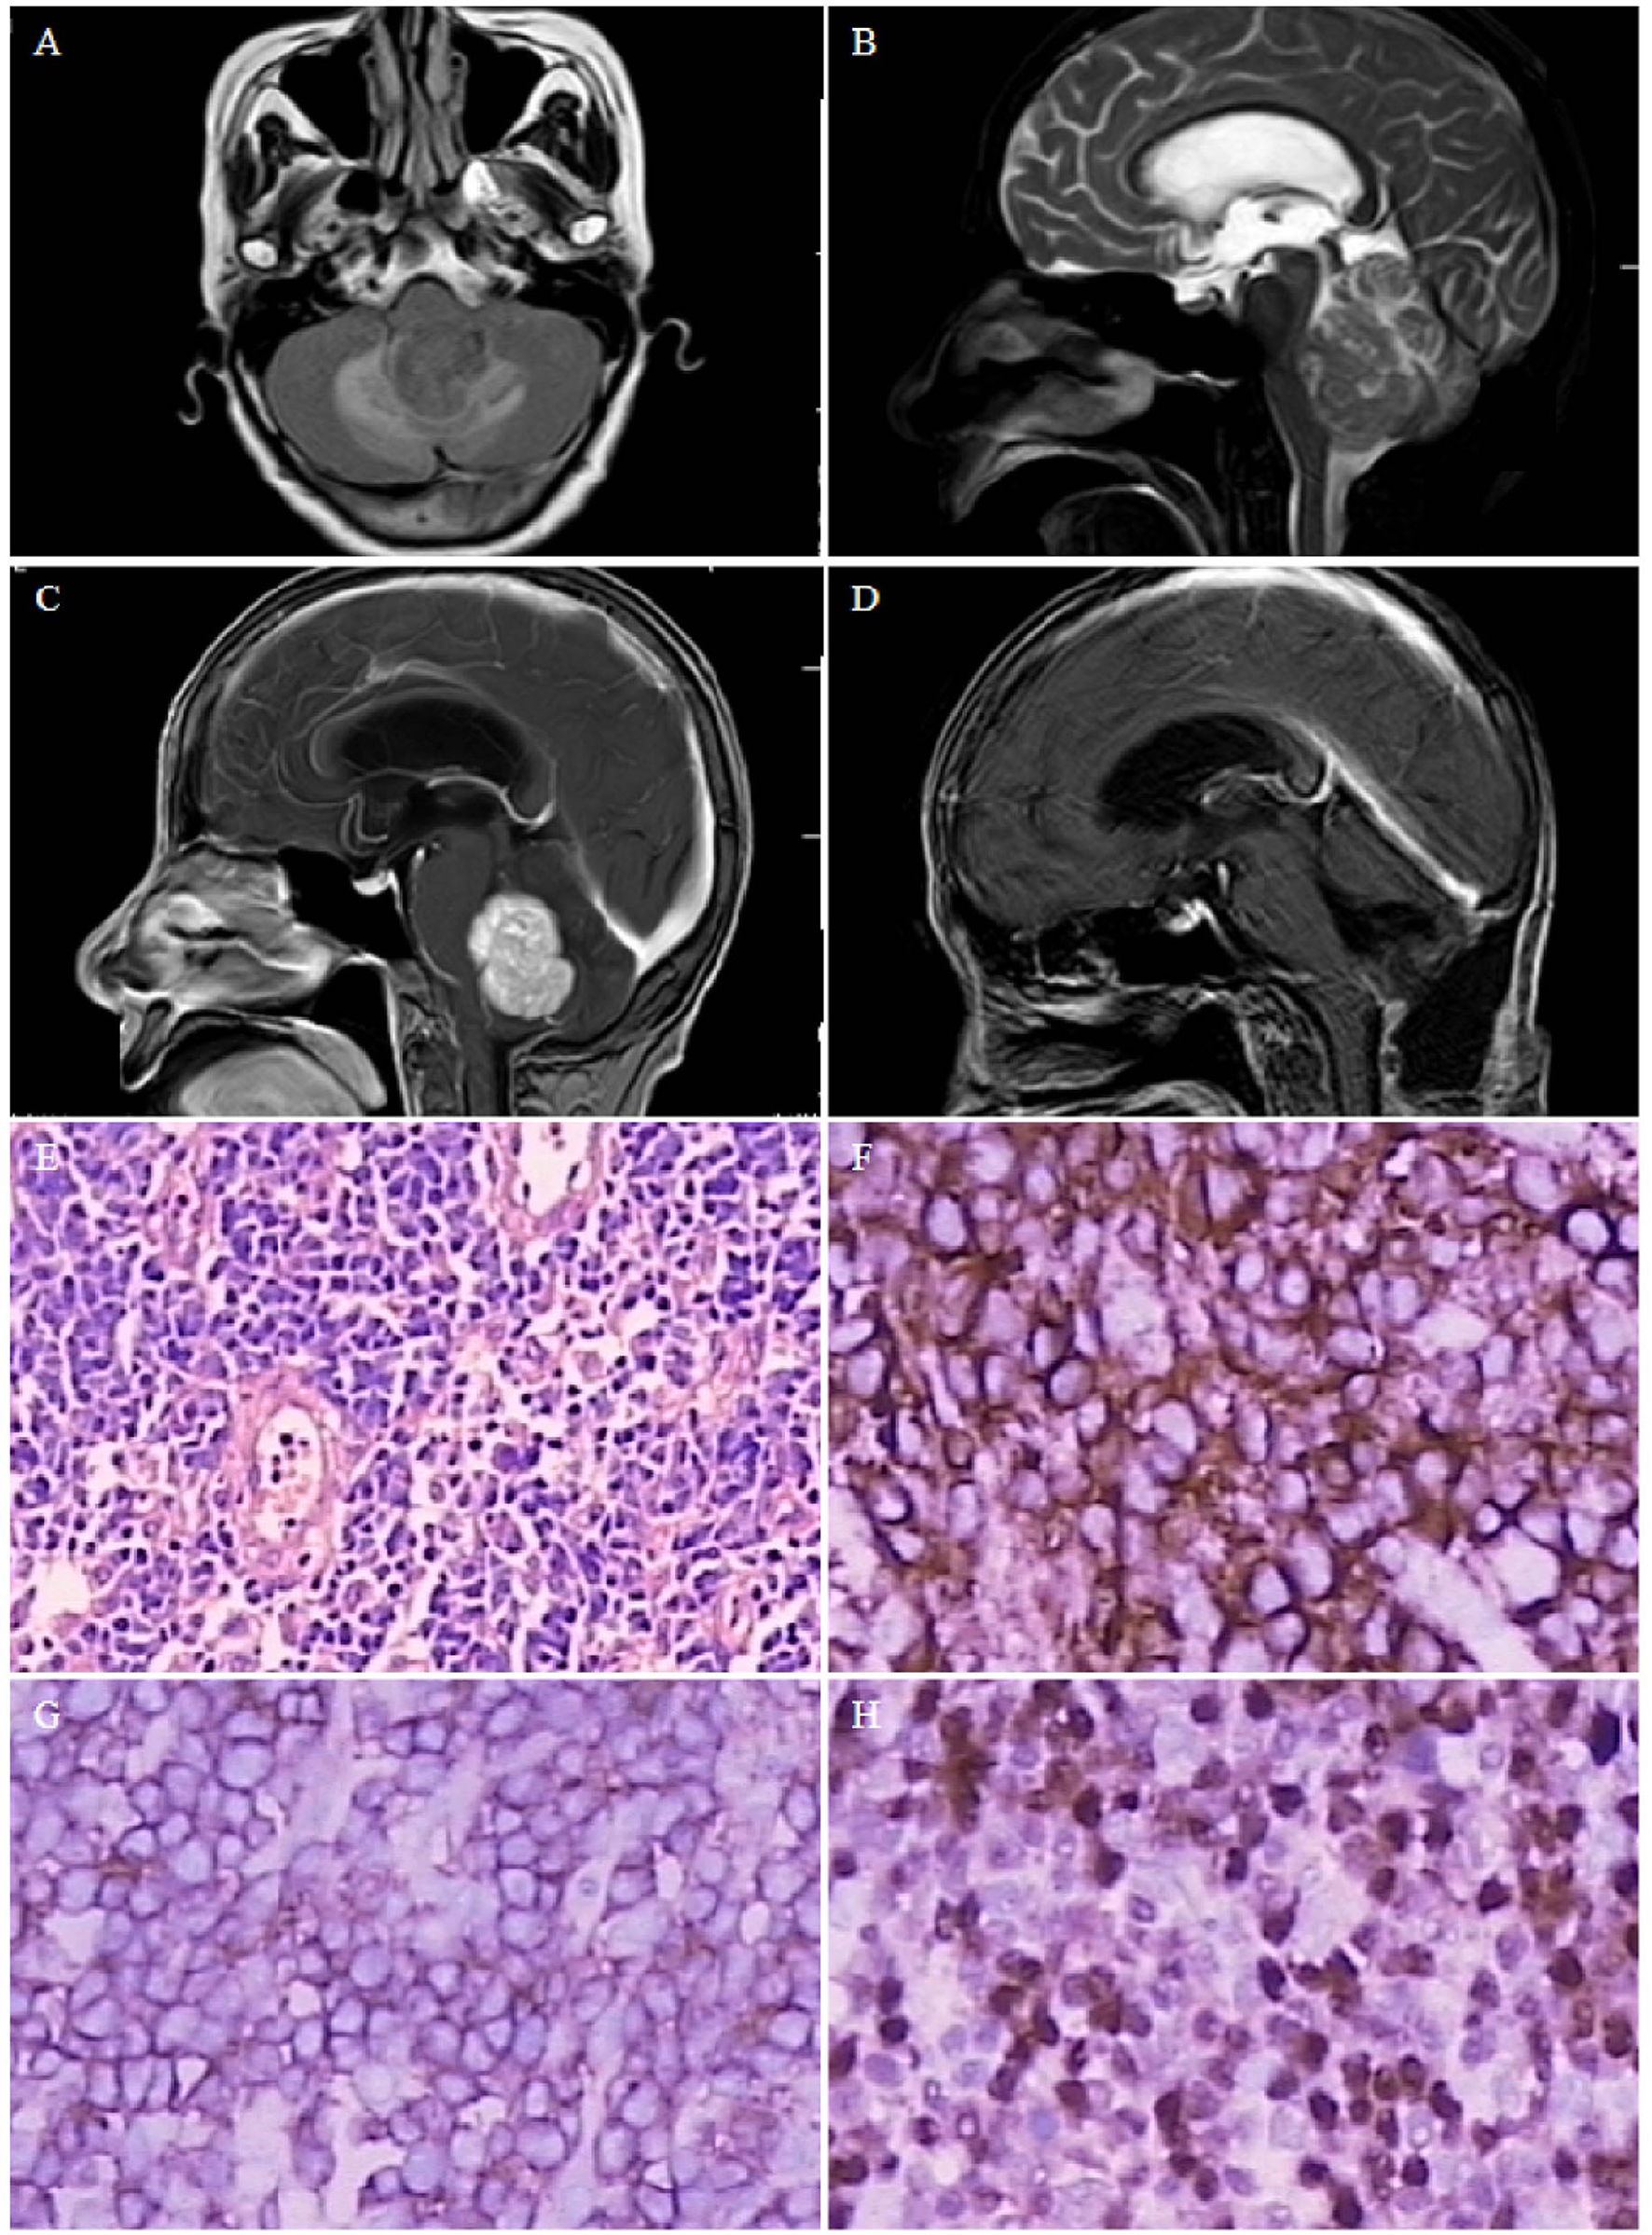

Case 1. Magnetic resonance image of a 4.0×2.8-cm solid mass in the fourth ventricle, with supratentorial hydrocephalus. (A) T1-weighted image showing low signal. (B) T2-weighted image showing low signal. (C) Homogeneous enhancement on contrast-enhanced T1-weighted images. (D) Postoperative magnetic resonance image showing no residual lesion, and obstructive hydrocephalus is relieved. Pathological microscopic examination shows diffuse large B-cell infiltration [(E) hematoxylin and eosin, 200× magnification], including CD20- [(F), 400× magnification], LCA- [(G), 400× magnification], and MUM-positive [(H), 400× magnification] lesions.

A 69-year-old woman presented with headache and dizziness for 2 months, and weakness in both legs 1 week before admission. The patient had previously developed ocular fundus pigmentation, resulting in blindness in both eyes. No immune deficiency or other underlying diseases were noted. The patient underwent head imaging 4 months before admission, which only indicated white matter thinning. Physical examination revealed no obvious positive signs. Brain MRI revealed a 4.0×2.8-cm solid mass in the fourth ventricle (Figure 2), which was considered a medulloblastoma or solid hemangioblastoma. The patient and her family opted for surgical resection. The surgery was performed via a prone postero-medial approach. During the operation, the tumor was observed to originate from the lateral orificium choroid plexus of the fourth ventricle with an abundant blood supply. Complete tumor resection was achieved under electrophysiological monitoring. Histopathological examination revealed diffuse large B-cell infiltration (Figure 2E), with positive immunochemical staining for CD20, LCA, and MUM (Figures 2F–H, respectively). The diagnosis was primary DLBCL of the fourth ventricle. The patient developed complications of pulmonary infection, recovered, and was discharged after 2 months of antibiotic treatment. The patient refused further chemoradiotherapy and died 15 months after surgery due to tumor recurrence.